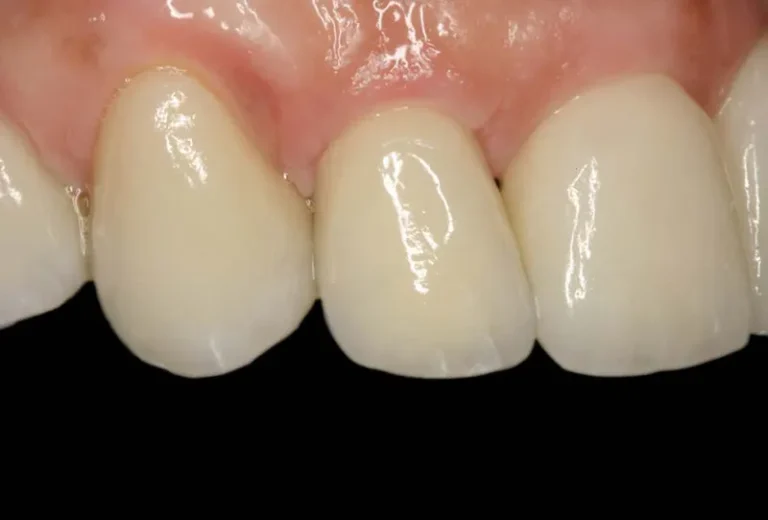

La osteointegración es el proceso biológico fundamental que determina el éxito de los implantes dentales. Durante este fenómeno, el hueso del maxilar crece y se fusiona directamente con la superficie del implante de titanio, creando una conexión estructural y funcional que garantiza la estabilidad a largo plazo. Este proceso, descubierto por el profesor Per-Ingvar Brånemark…

La sanación de un implante dental es un proceso gradual que varía según cada paciente. Generalmente, la integración completa del implante con el hueso (osteointegración) tarda entre 3 y 6 meses, aunque la recuperación inicial de los tejidos blandos ocurre en las primeras semanas. Durante este período, es fundamental seguir las indicaciones del especialista para…